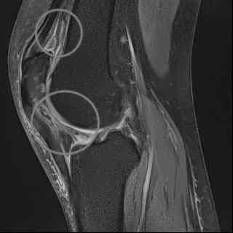

MRT bei Arthrofibrose im Knie

Bei Verdacht auf eine Arthrofibrose kann der Orthopäde eine Kernspintomographie (MRT) anfertigen. Die MRT zeigt Veränderungen der Weichteilstrukturen im Gelenk. Auf diese Weise kann der Arzt neben Bandapparat, Menisken und Knorpel auch die Gelenkkapsel beurteilen, die bei einer Arthrofibrose verklebt ist. Auch die für Arthrofibrose typischen Wucherungen durch das Narbengewebe erkennt der Spezialist in der MRT-Aufnahme.